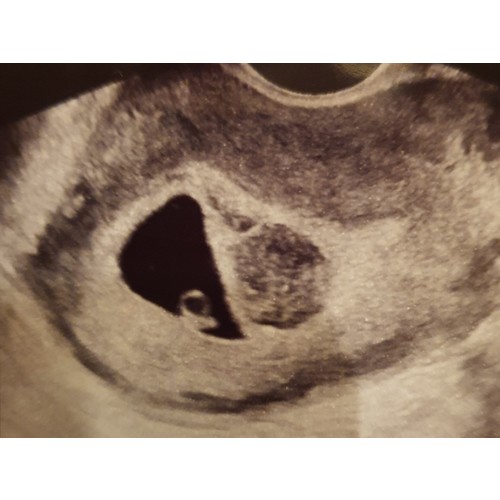

Ja vanmorgen om 9 uur! Vanmorgen thuis rood bloedverlies dus ik voelde m al aankomen maar we zagen een kloppend hartje! Grootte klopte ook precies met de termijn maar het bloedverlies zit me niet lekker. Pal naast de vruchtzak zit ook een ronde grijze vlek waarvan ze niet weet wat het is, kan een vleesboom zijn.. Vrijdag weer een echo🙏